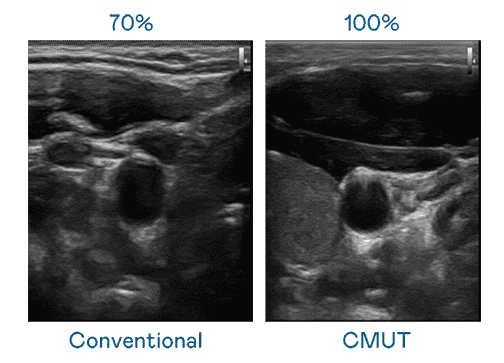

CMUT 技术是一种用电容式微机电元件来产生超音波讯号的技术。。。。与传统 PZT 压电式技术相比,,,,CMUT 频宽增加 30%,,更宽频的超音波讯号让影像解析度大幅提升,,,,是实现高影像品质医疗超音波扫描、、促进精准医疗发展的关键技术。。。。

大频宽带来超清晰影像

超音波影像的解析度高低,,,首先取决于探头能发出的讯号频宽。。。欧陆注册 CMUT 可提供高清晰的超音波讯号,,,提供高频宽、、、、高灵敏度、、、影像纹理细节更高的超音波影像,,,,协助医护人员缩短影像判读时间及利用精准的医疗影像进行诊断。。。。